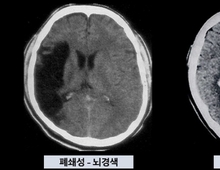

매번 MRI 찍는 대신…"간단 피검사로 뇌질환 경과확인 가능"

국내 연구진이 자기공명영상 촬영장치(MRI)를 대신해 혈액검사만으로 간단히 뇌 질환의 경과를 추적할 수 있는 나노기술 개발에 성공했다. 서울아산병원은 이 병원 신경과 이은재 교수와 의생명연구소 김진희 박사, 연세대학교 생명공학과 신용 교수 연구팀이 이 같은 연구 결과를 최근 도출했다고 11일 밝혔다. 서울아산병원에 따르면 대부분의 뇌 질환으로 인해 손상된 신경세포는 쉽게 회복되지 않아 이에 대한 조기 진단과 질병 활성도에 대한 모니터링이 중요하다. 그러나 뇌는 조직 검사가 힘들어 고비용 MRI를 반복 촬영해야 하는 데다가 영상 검사로는 미세한 변화를 정밀 추적하는 데 한계가 있다는 어려움이 있었다. 이에 연구팀은 먼저 특정 단백질의 구조를 모사해 표적 분자를 정밀하게 인식하는 '펩타이드 각인 나노복합체 기술'을 개발해 뇌와 척수에 존재하는 '성상교세포'만을 혈액에서 분리해냈다. 이후 연구팀은 서울아산병원 바이오뱅크에 보관된 혈청 시료 147개를 확보했다. 분석 대상에는 시신경척수염 스펙트럼 장애·다발성경화증·파킨슨병 등 환자의 혈청 시료와 건강한 이의 대조군 혈청이 포함됐다. 연구팀이 나노복합체 기술을 활용해 혈청 시료를 분석한 결과, 성상교세포 손상을 반영